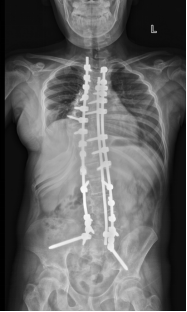

此次来我院的四名藏族患儿,均为重度脊柱侧弯,最严重者脊柱侧弯Cobb甚至高达120多度,脊柱严重变形,手术难度及风险高,在当地难以治疗。深圳市儿童医院骨科党支部心系藏族同胞需求,迎难而上,针对每一位藏族患儿的病情制定了个性化、精细化的诊疗方案。从术前详细的脊柱畸形评估、三D打印重建,到术中精准的脊柱畸形截骨矫正,再到术后全面科学的康复指导,先后成功为藏族患儿进行了脊柱侧弯矫正,帮助他们挺直了脊梁。

看到藏区孩子们经过治疗后,原本弯曲的脊柱逐渐挺拔,罗新乐书记强调,深圳市儿童医院始终秉持“一切为了孩子”的宗旨,积极发挥儿童医疗中心的辐射作用,为包括藏族同胞在内的广大患儿提供高质量的医疗服务。医院将继续加强藏区医疗帮扶,守护民族未来脊梁,为孩子们的健康成长保驾护航!